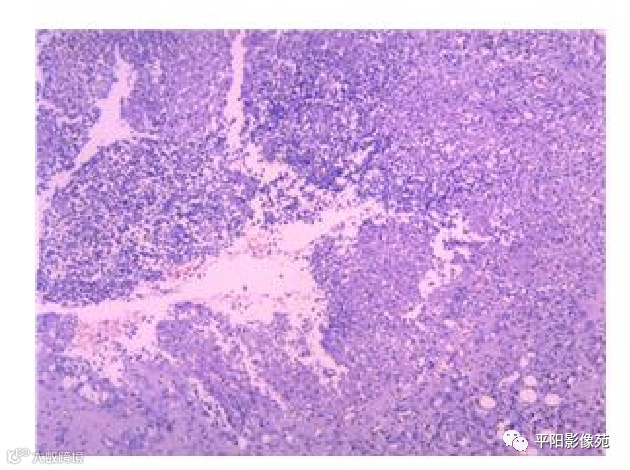

病理结果

部分胃壁)送检增生的纤维脂肪组织内可见大量急慢性炎细胞浸润,部分区域脓肿形成,边缘可见大量炎性坏死组织,结合临床符合穿孔的病理改变